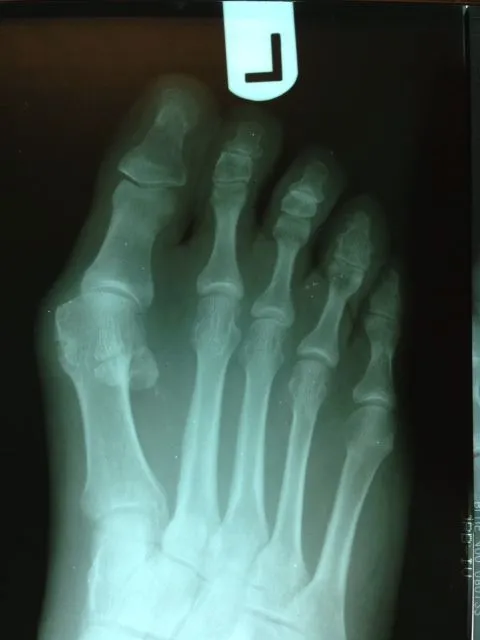

Before and immediately postop S/P bunionectomy

Before and 6 months status post bunionectomy.